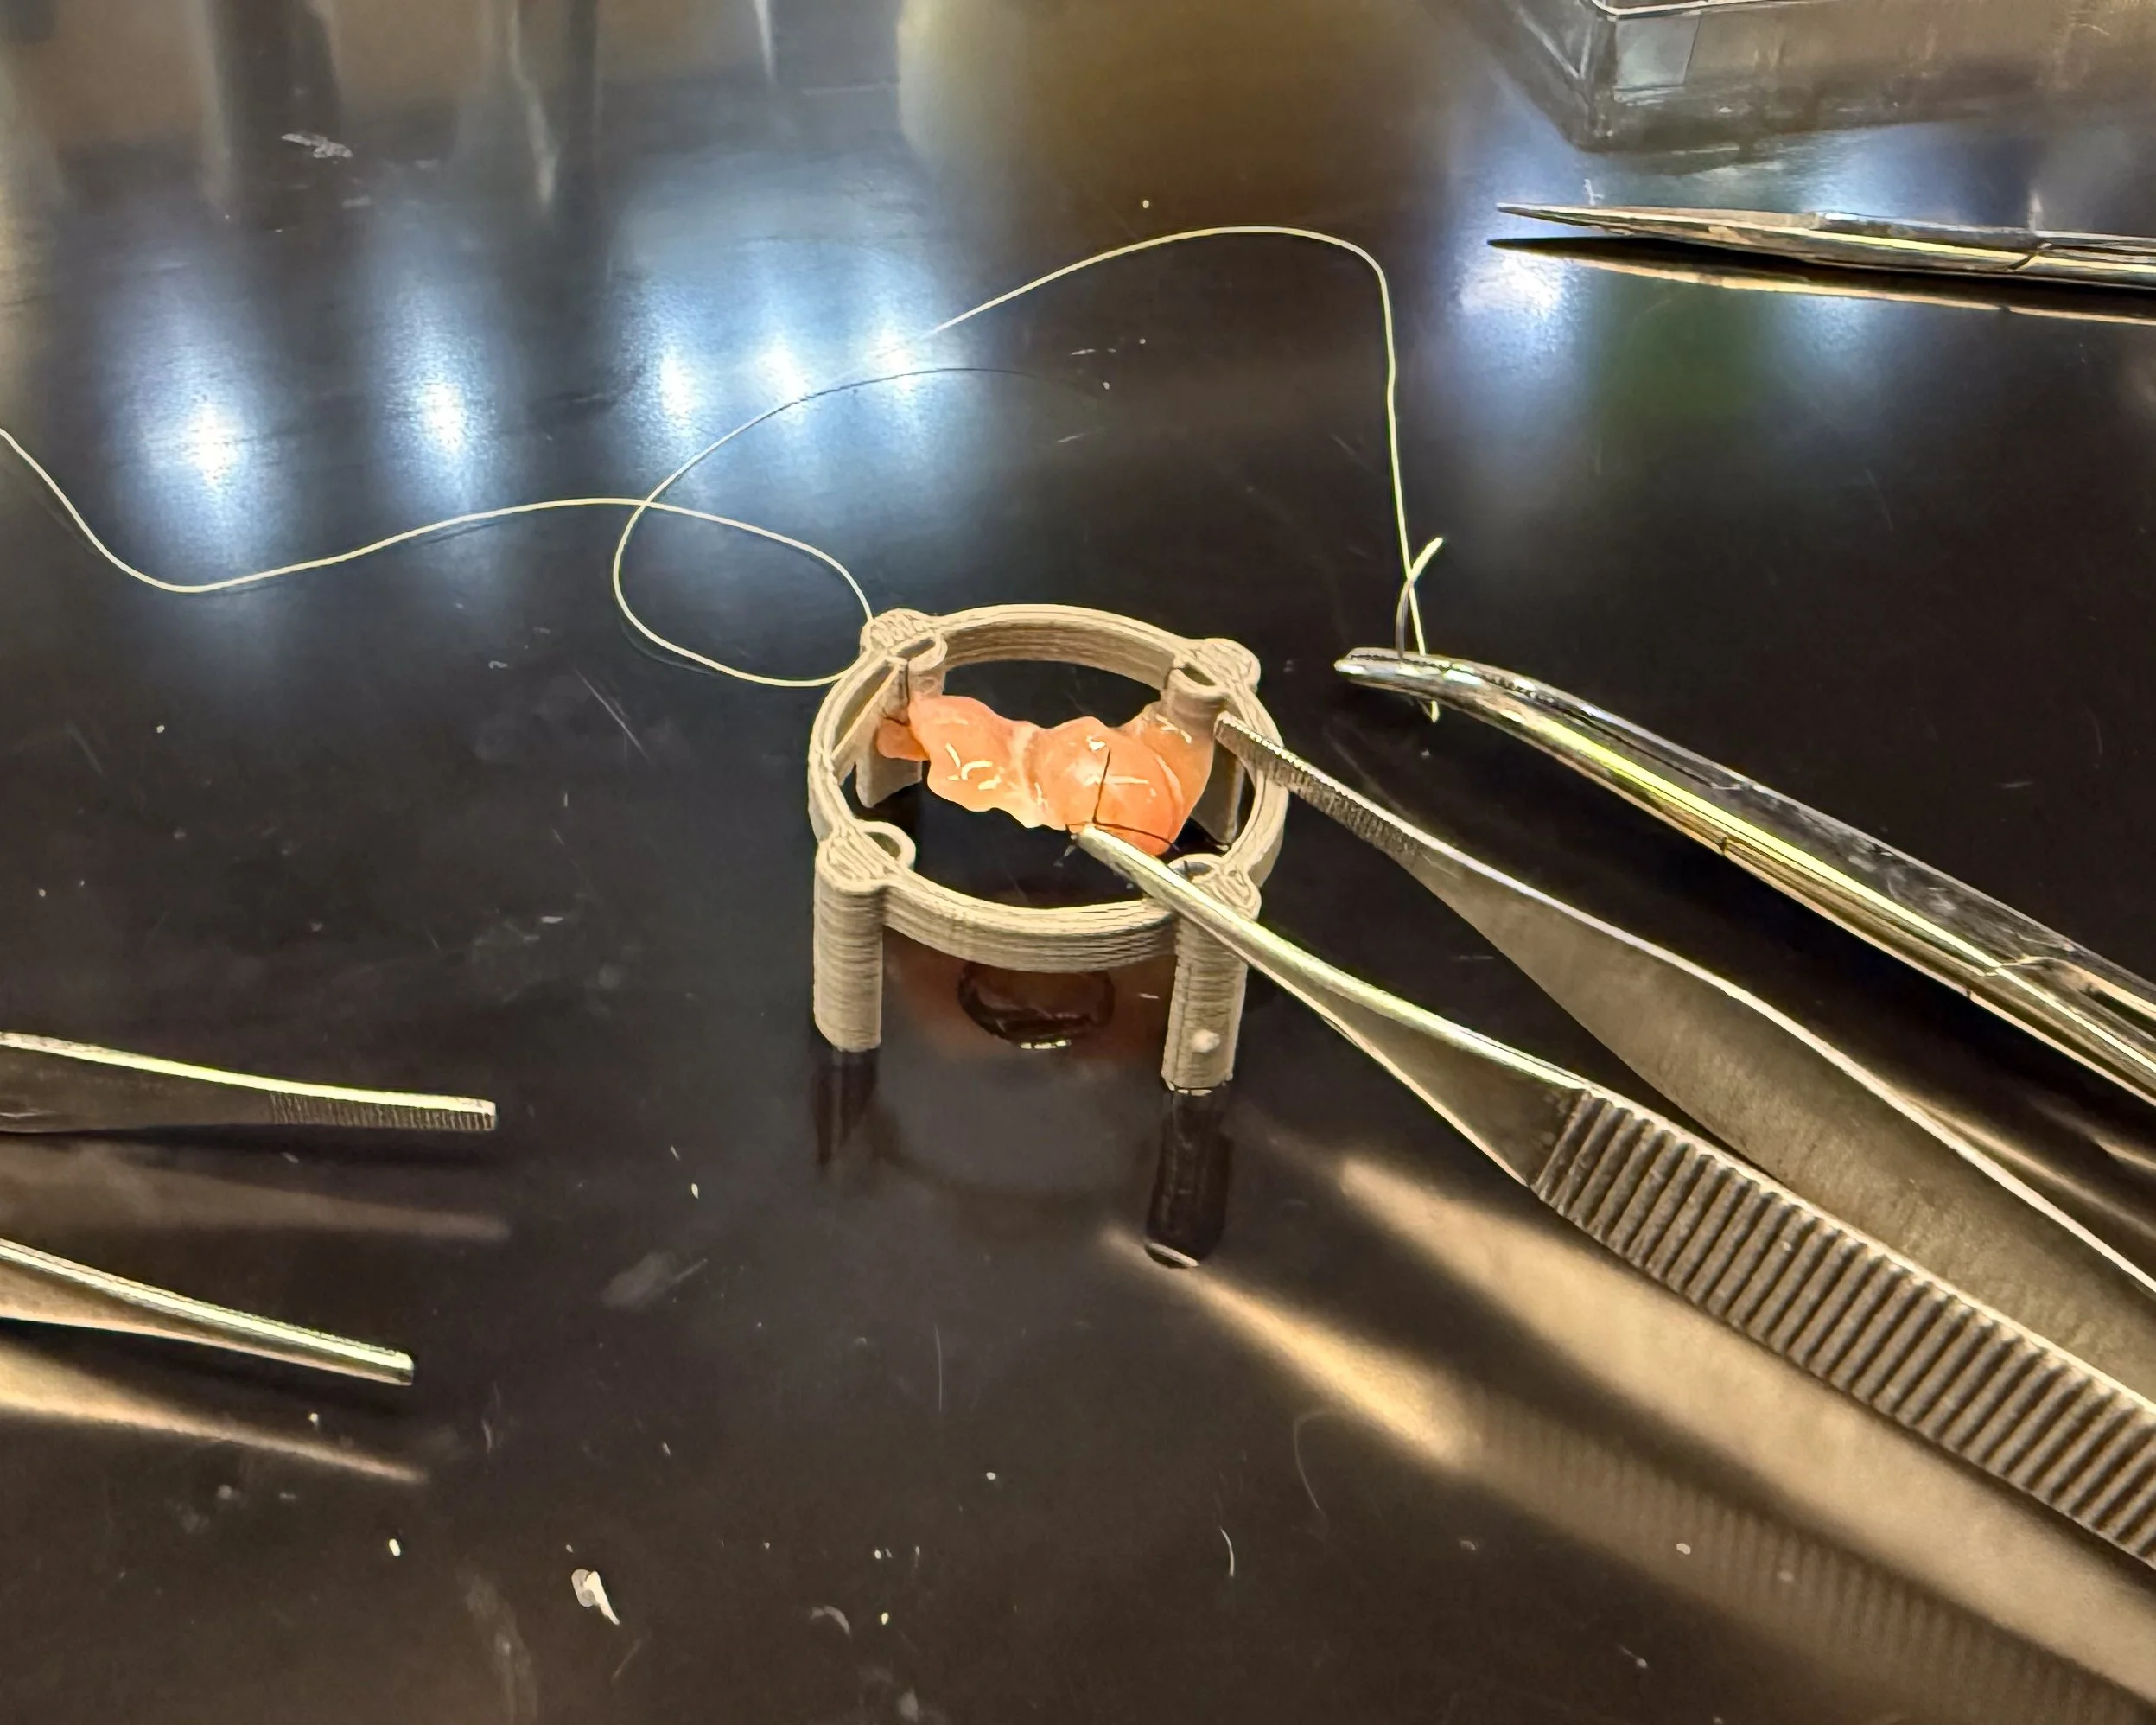

Gallery: DMM in development at the Sarcogenics lab

Remove cells, keep structure

Donor muscle tissue is processed to strip away all living cells, leaving behind the extracellular matrix — a natural scaffold made of proteins like collagen, laminin, and fibronectin.